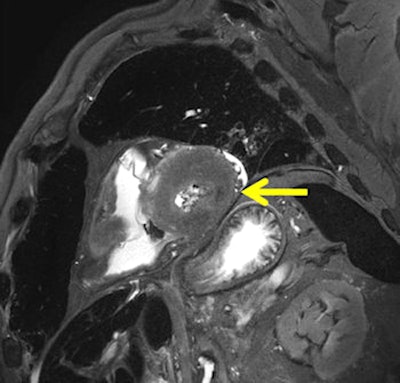

Findings of cloudy hypointense myocardial areas in T2-weighted images without any hyperintense marginal edematous reaction were diagnosed as peracute ischemic lesions, and were not visible at autopsy, Jackowski and colleagues wrote.

Among the 76 cases, postmortem analysis identified 124 myocardial lesions (chronic = 25, subacute = 16, acute = 30, and peracute = 53), the team wrote. They found excellent correlation among myocardial findings at autopsy and chronic, subacute, and acute infarction cases. Peracute infarction areas detected at postmortem MRI were verified by histology in 62.3% of cases, and could be related to a matching coronary finding in 84.9%, they wrote.

The study is the first to amass a large number of cases presenting with hypointense T2-weighted lesions that are well-correlated to coronary events; among the 42 cases, there were 53 hypointense T2-weighted lesions that remained invisible at macroscopic dissection, the authors wrote.